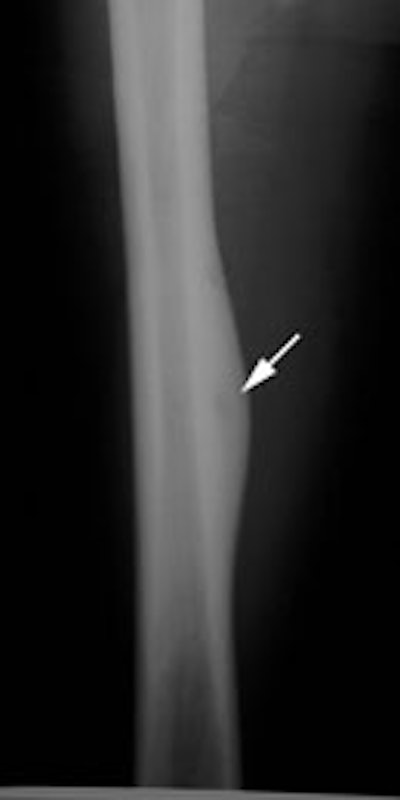

|

Right femoral osteoid osteoma: Flow (click to enlarge) and blood pool images demonstrated a focus of increased activity within the right mid-femoral diaphysis (black arrows). Intense tracer accumulation could be seen in this region on the delayed images. A delayed right medial spot image demonstrated a focal area of even greater activity (blue arrow) within the diffuse abnormality corresponding to the lesions nidus. Plain film (click to enlarge) demonstrates the characteristic appearance of an osteoid osteoma with a dense region of reactive sclerosis surrounding a central area of lucency (white arrow) (click image to enlarge) |